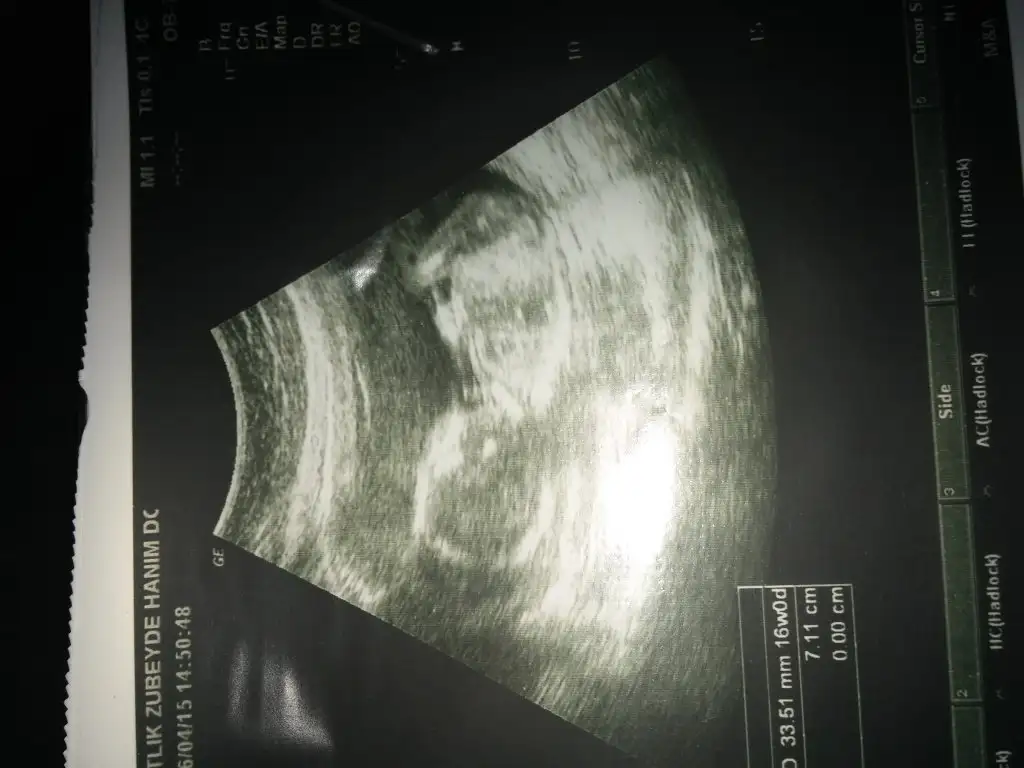

Kizlar 3 lu taramayi yaptirdim geldim.dr bisey demedi 11 gun sonra sonra sonucu alinca gosterirse soylerim dedi. :KK69:

• 20150406_110922.webp

20150406_110922.webp

30,7 KB · Görüntüleme: 120

Canım ben senin bebeğinin önceki fotoğrafını da hatırlıyorum bana hep kız gibi geliyor.